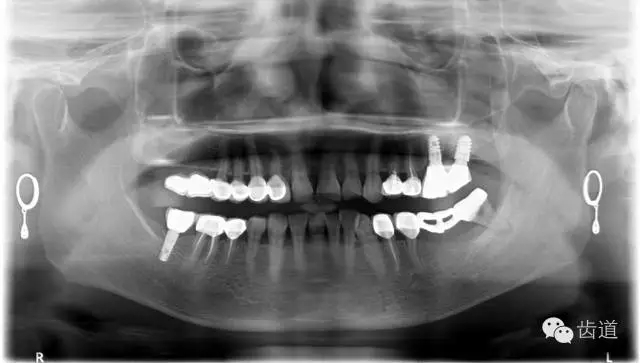

1、術(shù)前全景片

2、45,46術(shù)前片顯示根管上段充填物,根管影像不清晰,少許根尖暗影

3、34術(shù)前片顯示遠(yuǎn)中面暗影近髓

1、45,46牙體缺損,慢性根尖周炎(不良根管治療術(shù)后)

2、34慢性牙髓炎

3、慢性牙周炎

4、牙列缺損

5、不良修復(fù)

4、 全景片